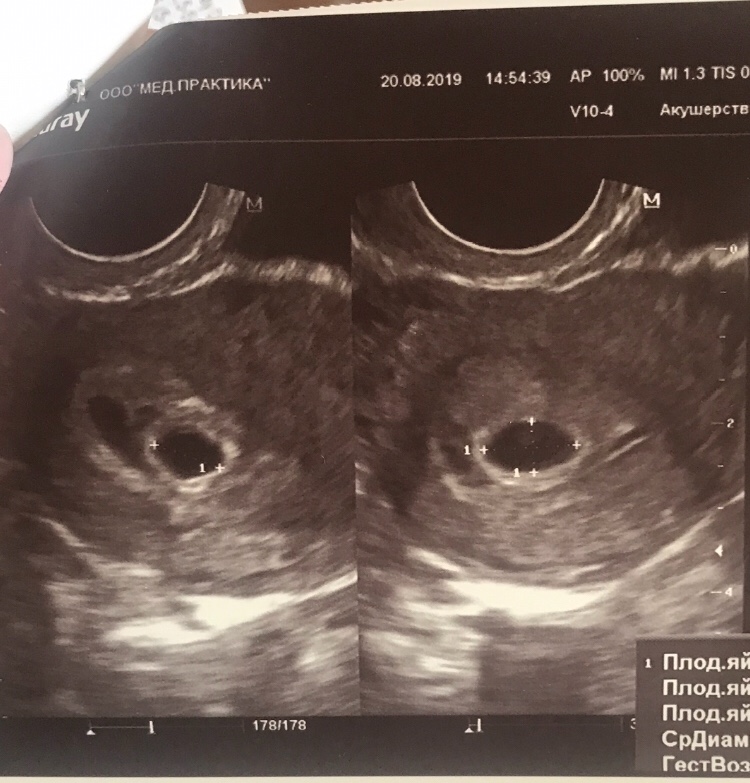

Следующее обязательное скрининговое ультразвуковое исследование проводится в 20-21 неделю беременности. При этом обязательно проводят измерения плода, чтобы оценить, нет ли отставания в росте. Ведь при кислородном голодании замедляются темпы роста плода и размеры его начинают отставать от нормы для каждого срока беременности. Кроме того врач обязательно оценивает состояние и зрелость плаценты. Во время УЗИ проводится также допплерометрия сосудов матки для выявления ранних изменений, предшествующих клиническим проявлениям плацентарной недостаточности.

Третье УЗИ проводится всем будущим мамам в 30–34 недели беременности. Врач измеряет окружность головы и живота крохи, длину костей его ручек и ножек, и вычисляет предполагаемый вес плода.

Эти измерения позволяют доктору убедиться в том, что малыш развивается нормально. Также имеет значение строение плаценты, наличие в ней признаков старения, вследствие чего она обычно перестает полноценно снабжать малыша кровью, а, значит, ему перестает хватать кислорода и питательных веществ и развитие ребенка нарушается. Во время УЗИ оценивается количество и вид околоплодных вод, которые также могут изменяться при внутриутробном страдании плода.